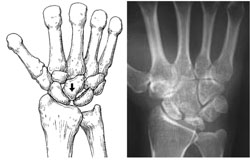

Stage 1. (Left) This illustration shows a fracture of the lunate during the early phase of the disease.(Right) An x-ray of a patient's wrist during Stage I shows no deterioration of the lunate bone.

Reproduced and adapted with permission from Allan CH, Joshi A, Lichtman DM: Kienböck's disease: diagnosis and treatment. J Am Acad Orthop Surg 2001; 9 : 128-136.

Stage 2. (Left) This illustration shows that the lunate has hardened with more than one fracture line. (Right) The lunate is brighter than the surrounding bones, which indicates that the bone is dying.